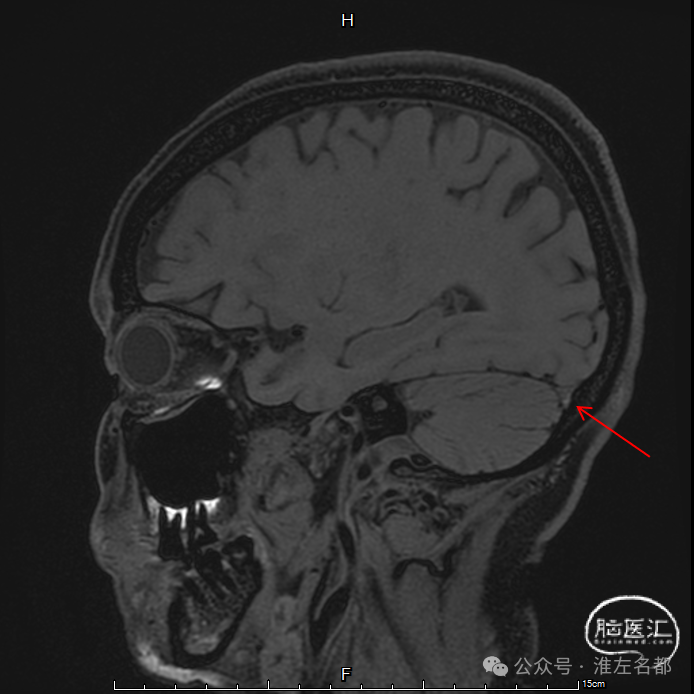

三维黑血高分辨T1

三维黑血高分辨T1平扫(上图)和增强(下图):右侧横窦慢性血栓。

三维黑血高分辨T1平扫(上图)和增强(下图):左侧横窦发育细小。